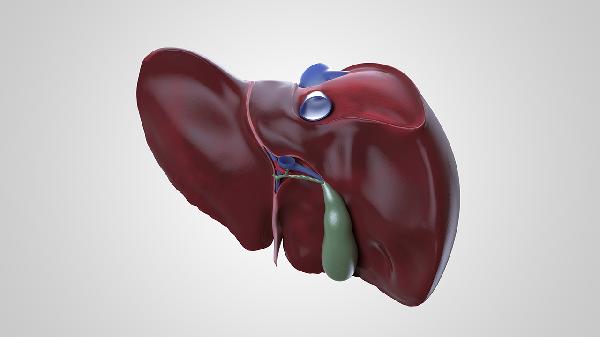

脂肪肝可能与肥胖、高脂饮食、胰岛素抵抗等因素有关,通常表现为肝区不适、转氨酶轻度升高、血脂异常等症状。超声检查可见肝脏回声增强,治疗可选用水飞蓟宾胶囊、多烯磷脂酰胆碱胶囊等护肝药物,配合有氧运动及低脂饮食。需定期监测肝功能及肝脏弹性检测。

肝硬化可能与长期酗酒、慢性肝炎进展有关,通常表现为腹水、蜘蛛痣、肝掌等症状。胃镜检查可发现食管胃底静脉曲张,治疗需使用呋塞米片、螺内酯片控制腹水,必要时行经颈静脉肝内门体分流术。饮食需限制钠盐摄入,每日蛋白质补充控制在每公斤体重1-1.2克。